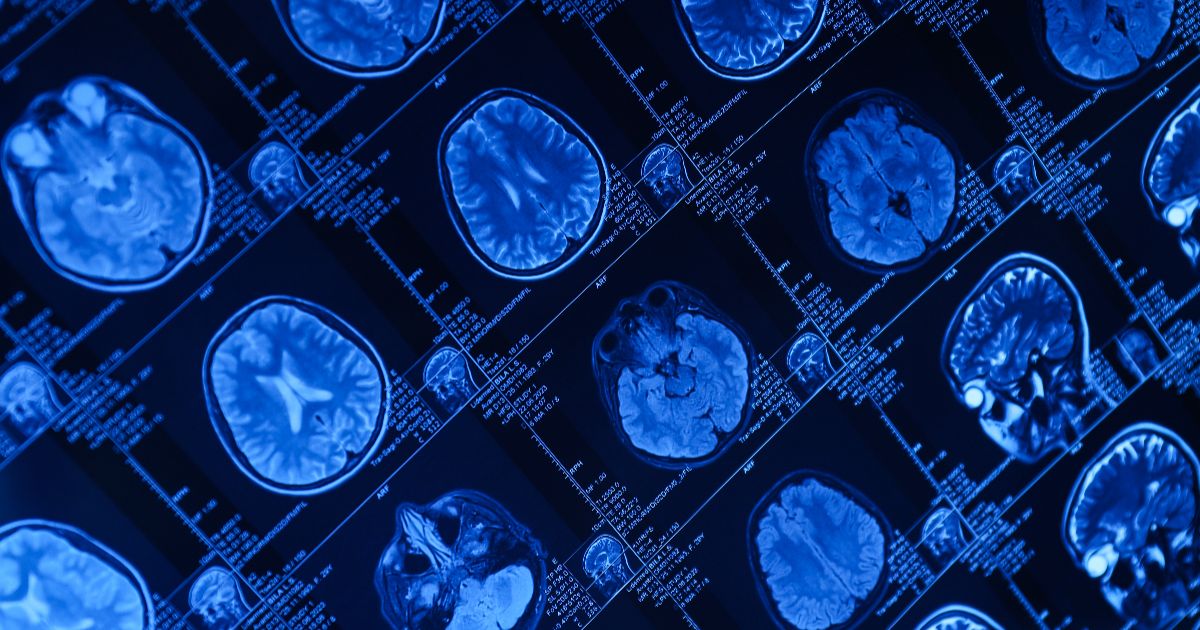

Functional MRI is a brain imaging test that shows how your brain works in real time.

Functional MRI, also called fMRI, measures brain activity by tracking changes in blood flow.

The scanner detects these small changes. A computer then creates color maps that show active brain areas.

Unlike a regular MRI, which shows brain structure, this test shows brain function.